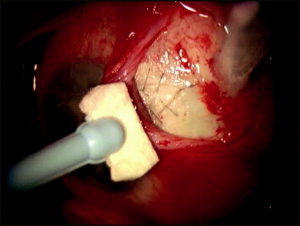

Because MMC can be highly toxic to the corneal endothelium and tissues of the anterior segment,[11][12] it should be applied in a controlled manner to bare sclera prior to entering the eye. A cellulose or cut end of a Weck-Cel sponge saturated with MMC is applied to bare sclera. We recommend diffuse application of multiple MMC sponges, under all areas of Tenon’s fascia, to decrease the incidence of high avascular localized blebs and to promote low diffuse filtering blebs. After the exposure period, the sponge is removed and the surgical site is thoroughly irrigated with a full container (15 mL) of balanced salt solution.